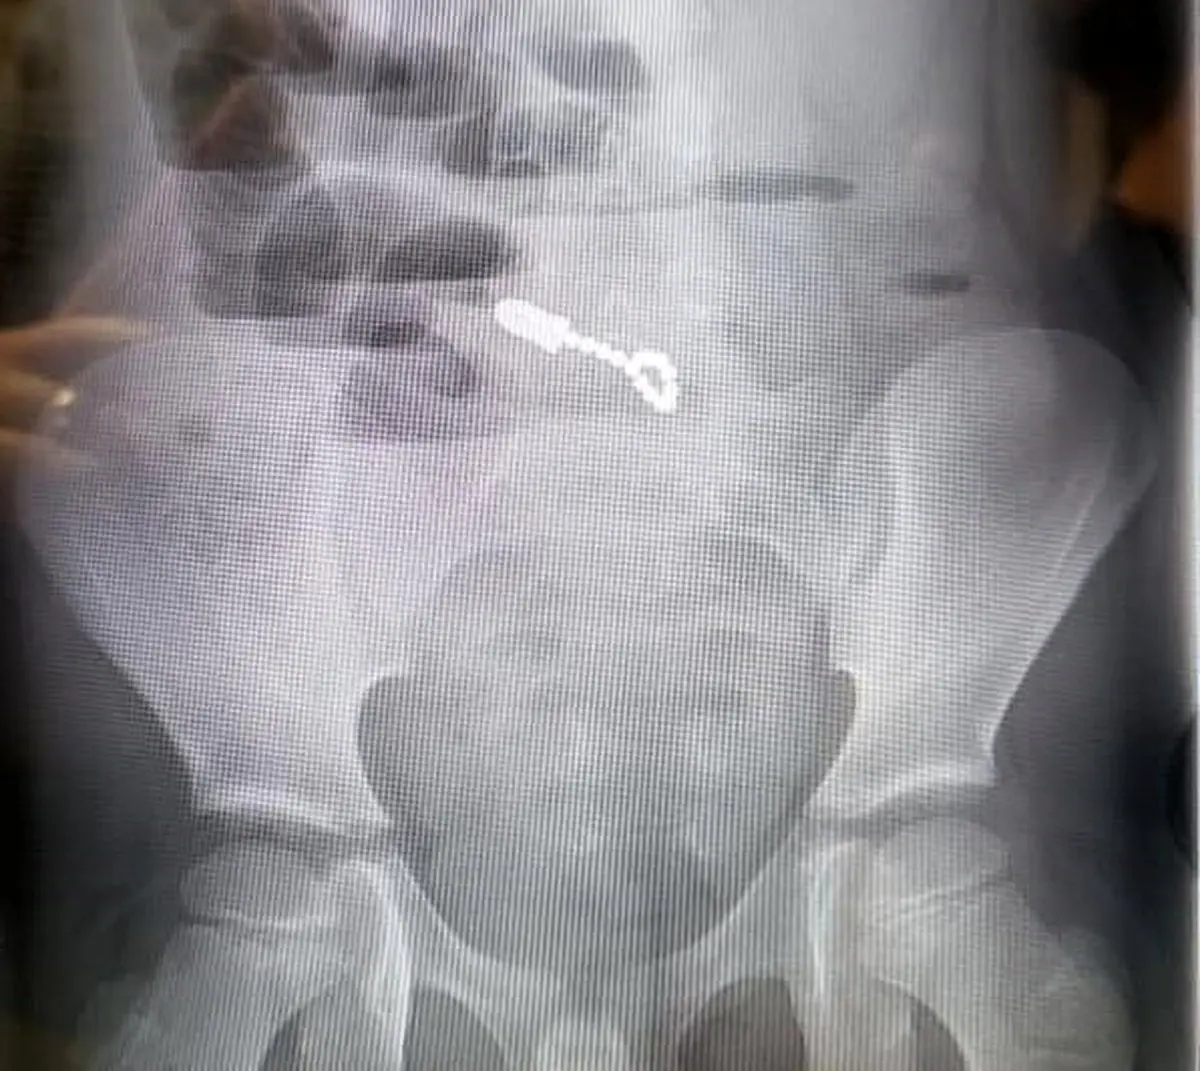

والدین یک پسربچه 6 ساله ساکن ایالت یوتا پس از آنکه به مدت سه روز شاهد استفراغ و دلدرد فرزندشان بودند تصمیم گرفتند وی را بهبیمارستان منتقل کنند، جایی که رادیوگرافی شکم این کودک وجود 14 قطعه کوچک آهنربا را در دستگاه گوارش وی به نمایش گذاشت. قطعاتی که بر اثر جذب یکدیگر به سوراخ شدن روده کوچک و نشت صفرا به دورن محوطه شکمی منجر شده بودند.